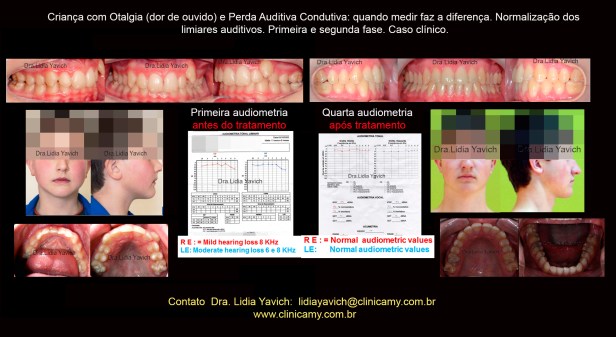

Paciente de sexo masculino com onze anos de idade se apresenta na consulta com queixas de dor de cabeça, dor na nuca, dor nos ombros, dor no pescoço, adormecimento e formigamento nas mãos e DIMINUIÇÃO DA ABERTURA BUCAL.

O paciente refere dor no ouvido esquerdo e sensação de entupimento nos ouvidos, principalmente do lado esquerdo. Também refere zumbidos em ambos os ouvidos e DIMINUIÇÃO DA AUDIÇÃO, EM AMBOS OS OUVIDOS.

Na história clínica do paciente em questão é relevante na análise do caso o antecedente de traumatismos no mento na primeira infância assim como as infecções repetitivas de ouvido e garganta e uma pneumonia que o paciente teve com oito meses e que precisou de internação hospitalar.

Imagens da oclusão habitual do paciente e vista oclusal superior e inferior. Fotografias do paciente sorrindo de frente e perfil no dia da consulta.

A primeira audiometria do paciente revela uma discreta hipoacusia no ouvido esquerdo e uma leve hipoacusia no ouvido direito.

A quarta audiometria do paciente após a finalização das duas fases do tratamento mantém os limiares normais no ouvido esquerdo e limiares normais no ouvido direito.

Comparação da primeira, segunda, terceira e quarta audiometria do paciente.

Normalização dos limiares no ouvido esquerdo e no ouvido direito.

Várias atividades físicas e psíquicas das crianças e adolescentes podem ser afetadas em função da diminuição da capacidade auditiva. A perda auditiva condutiva resultante da disfunção da tuba auditiva RESULTANTE DAS DESÓRDENS TEMPOROMANDIBULARES é MUITAS VEZES DESCONSIDERADA.

É de fundamental importância uma detecção precoce desta deficiência.